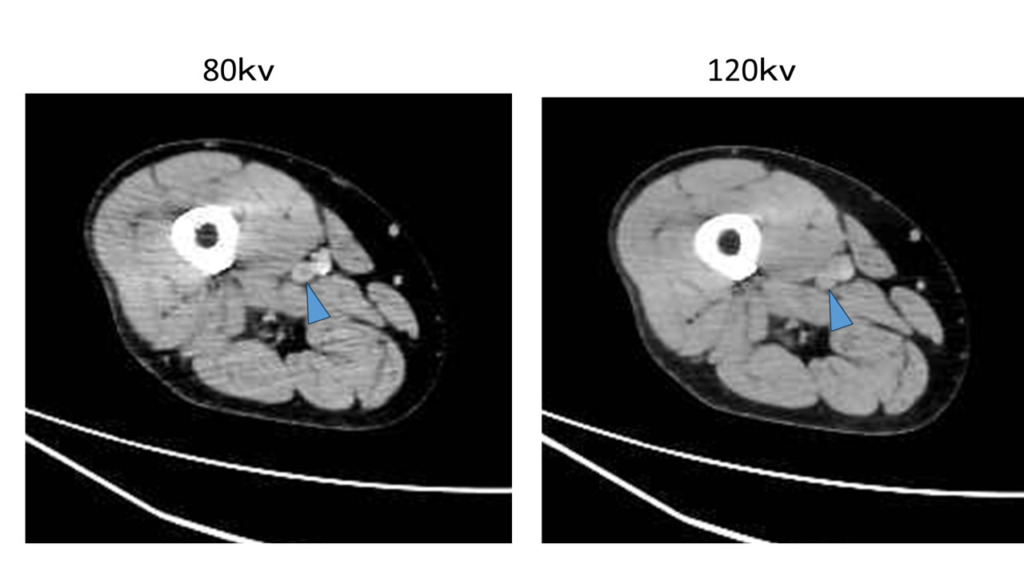

120kvで撮影した時の造影剤のCT値を1とした時の相対値では低電圧にするとCT値が1.6と上がり、120kvでの撮影した時と同じ造影効果を得るために必要な造影剤量も62%と減らせます。

実際の画像ですが、

120kV と比べるとCTは上がっていることがわかります。

当院の臨床画像でも

80kvで撮影した方がDVTの描出が良くなっています。

その他にも低電圧で撮影するので光子量が減るため、被ばく量が少なくなるというメリットもありますが、ただし注意が必要なのは電圧を下げることによって透過するエネルギーが低くなるので120kvと比較するとノイズが多くなります。